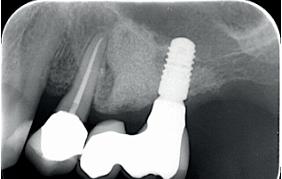

In een eerder artikel in Dentista (2019 issue 5) met de titel ‘Champignon of tulp?’ schreven we dat op basis van wat wij aan complicaties krijgen verwezen, het erop lijkt dat men ervan uitgaat dat overhang bij restauraties op implantaten geen probleem is. Gezien de bekende negatieve effecten van overhangende restauraties op het parodontium bij natuurlijke gebitselementen, is het echter niet verrassend dat implantaatgedragen suprastructuren met een paddenstoelachtige vorm problemen veroorzaken. In feite is het falen bij deze vormgeving al vanaf het ontwerp ingebouwd (afbeelding 1a-d).

In een meer recent artikel in Dentista (2020 issue 4), getiteld ‘De ideale vorm’, werd benadrukt dat de ‘emergence angle’ bij bone-level implantaten een belangrijke factor is in de ontwikkeling van peri-implantaire ontstekingen. Retrospectief onderzoek toont aan dat de prevalentie van peri-implantitis significant hoger is bij een emergence hoek groter dan 30 graden, vergeleken met abutments waarbij deze hoek kleiner is dan 30 graden. Recent werd dit opnieuw onderbouwd in een preklinische studie, waarin restauraties werden geplaatst met een emergence-profiel variërend van 20, 40, 60 of 80 graden (Strauss et al., 2024). Na 24 weken bleek dat grotere restauratieve hoeken leiden tot meer marginaal

botverlies. De auteurs concluderen daarom dat het verstandig is om de hoek zo smal mogelijk te houden, bij voorkeur onder de 40 graden. In de praktijk blijkt echter dat het niet altijd mogelijk is om een zo klein mogelijke restauratiehoek te gebruiken. Bijvoorbeeld wanneer er sprake is van een beperkte intermaxillaire ruimte. Om goed uit te komen met de suprastructuur zou dan een grotere restauratiehoek gebruikt moeten worden.

Bij bone-level implantaten met platform-switching is de diameter van het abutment op implantaat niveau kleiner dan die van het implantaat. Hierdoor is het risico groter dat, om occlusaal voldoende breedte te verkrijgen, er een te grote emergence angle ontstaat, wat resulteert in een te bolle kroon. Daarom is het bij de keuze voor een platform-switch implantaat in de basis essentieel om ofwel een implantaat met een grotere diameter te selecteren, ofwel het implantaat relatief dieper te plaatsen. Dit helpt om een optimale emergence te verkrijgen met een geschikte hoek en bolling vanaf het abutment naar de implantaatkroon.

1a-d. Een mooi vormgegeven kroon op element 47, maar deze ligt als een balkon bovenop de gingiva, waardoor het implantaat niet te sonderen is – laat staan dat de patiënt het goed kan reinigen.

een implantaat met een grotere diameter te plaatsen. In veel klinische situaties is dit echter niet mogelijk, waardoor een aangepaste vormgeving overwogen moet worden. Onze boodschap in de vorige twee artikelen was: denk in dergelijke gevallen in termen van een ‘premolaar’. Deze vormgeving sluit beter aan bij de afmetingen van een implantaat en biedt een voorspelbaardere langetermijnprognose.

Met in het achterhoofd dat het premolariseren van suprastructuren een gunstiger emergence profile geeft en een eenvoudiger te reinigen peri-implantaire situatie oplevert, bracht dit ons, naar aanleiding van een artikel van Aglietta et al. (2009), ertoe om in diverse casussen te kiezen voor een molaar die is vormgegeven als een premolaar met een kleine dummy. Maar zoals al gezegd, gebeurde dit schoorvoetend, omdat we ons ervan bewust waren dat kroon- en brugwerk met cantilever extensies op natuurlijke gebitselementen lagere overlevings- en succespercentages vertonen na een periode van 5 en 10 jaar (Pjetursson et al., 2004). De voorspelbaarheid op lange termijn voor implantaten was echter onduidelijk. Daarom was de uitkomst van de systematische review van Aglietta et al. (2009) interessant, omdat deze auteurs de overlevingspercentages van reconstructies op implantaten met cantilevers probeerden vast te stellen na een observatieperiode van mini-

maal 5 jaar. Hun conclusie was dat dit type restauratie kan worden beschouwd als een voorspelbare en betrouwbare vervanging van ontbrekende molaren bij gedeeltelijk edentate patiënten. Er werden geen nadelige effecten op het botniveau waargenomen rondom implantaten in de nabijheid van de cantilever extensies. Het onderzoek van Tuna et al. (2019) laat zien dat onze veronderstelling klopt: een kroon met een kleine dummy zorgt voor betere approximale reiniging, waarbij er dichter bij het implantaat gereinigd kan worden.

Afbeelding 2a-c. In deze casus is te weinig intermaxillaire ruimte om vanaf een platform-switch implantaat met een optimaal emergence profile tot aan het occlusale niveau te komen.